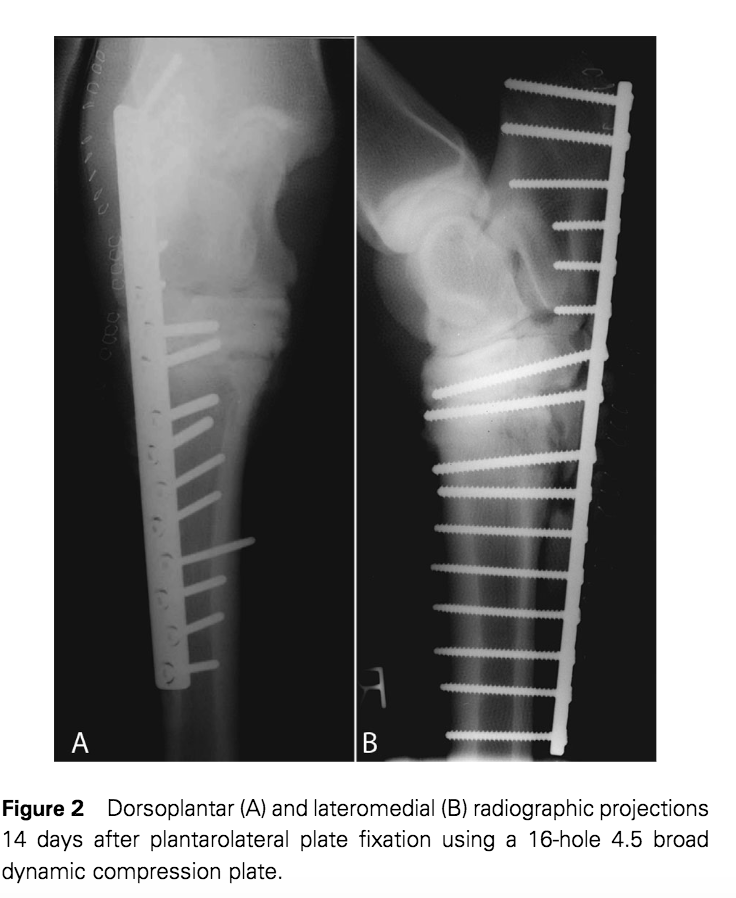

2) Open reduction and internal fixation/arthrodesis (cartilage removal (drilling) and LCP application) plus shorter period of external coaptation